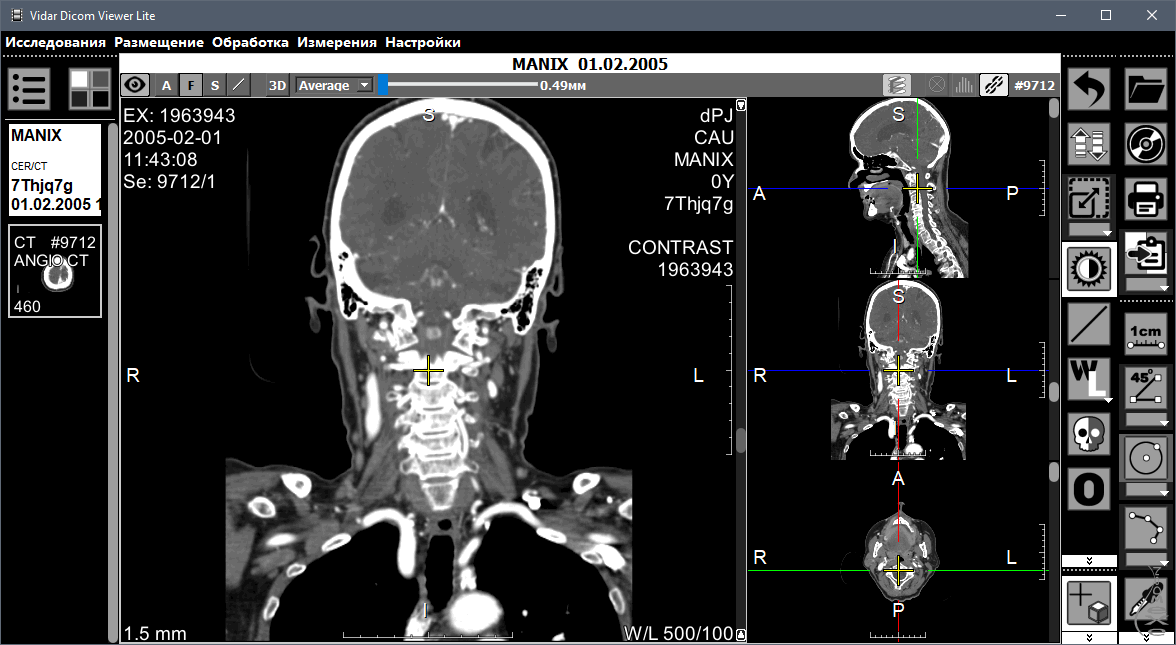

Лазерная камера для печати медицинских изображений на пленке стандарт dicom